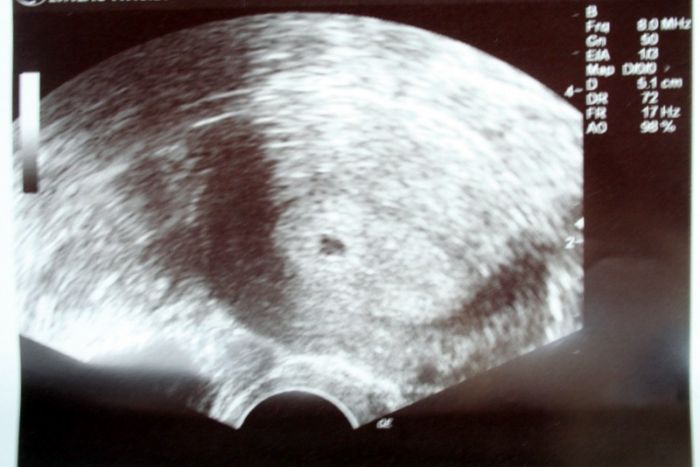

Jinak máme 0,5cm a přikládám fotečku , ta menší je oskenovaná a ta větší je focená foťákem ..

[411273] Dneska jsme 5+0 , tak že ukončený pátý a začátek šestého .